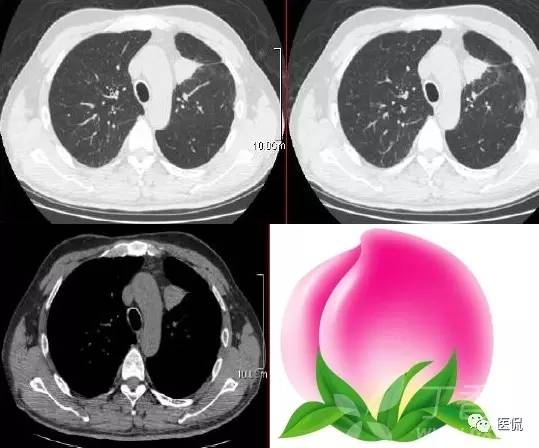

桃尖征

指肿块某一边缘尖角状突起形似桃尖,是炎性假瘤包膜的粘连牵拉,为良性肿块尤其是炎性假瘤特有。由于肿瘤大多位于肺的浅表部位,邻近胸膜常出现炎性反应,继之局限性的胸膜增厚、粘连,于肿物边缘可见类似胸膜幕状粘连的尖角状表现,这种尖角和肿块连在一起酷似一个桃子的桃尖。假瘤的主体和胸膜的炎性牵拉形成的尖角常常和周围胸膜、心包及纵隔粘连形成桥样结构及宽桥征;炎性假瘤的形成,一般被认为是感染后非特异性炎症的机化修复而引起的局限性慢性瘤样增生,形成的肿块压迫周围肺组织周围组织反应性改变,形成假包膜,所以一般边界广整,少数包膜不完整、无包膜或有胸膜粘连者,边缘可不光整。炎性假瘤依据细胞成分为组织细胞瘤型、硬化血管瘤型、浆细胞肉芽肿型、细胞上皮乳头痒增生等五个类型。肿块形态不规则和肿块分叶是病灶在病理上不同组织、不同数目因而生长速度不同所致;而边缘光滑的炎性假瘤则是同类组织以同等的生长速度增生形成。假瘤的分叶一般较浅或没有分叶,多为单发,两肺各叶均可发生,右侧多于左侧,下叶多于上叶。炎性假瘤可以有如下表现:

炎性假瘤桃尖征:

炎性假瘤(病灶形态不规则,边缘可呈刀切样,周围可见毛玻璃样改变,强化异常明显):